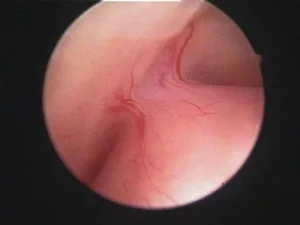

O pólipo uterino, também conhecido como pólipo endometrial, consiste no crescimento excessivo de células na parede interna do útero, formando bolinhas semelhantes a cistos que se estendem para o interior do útero.